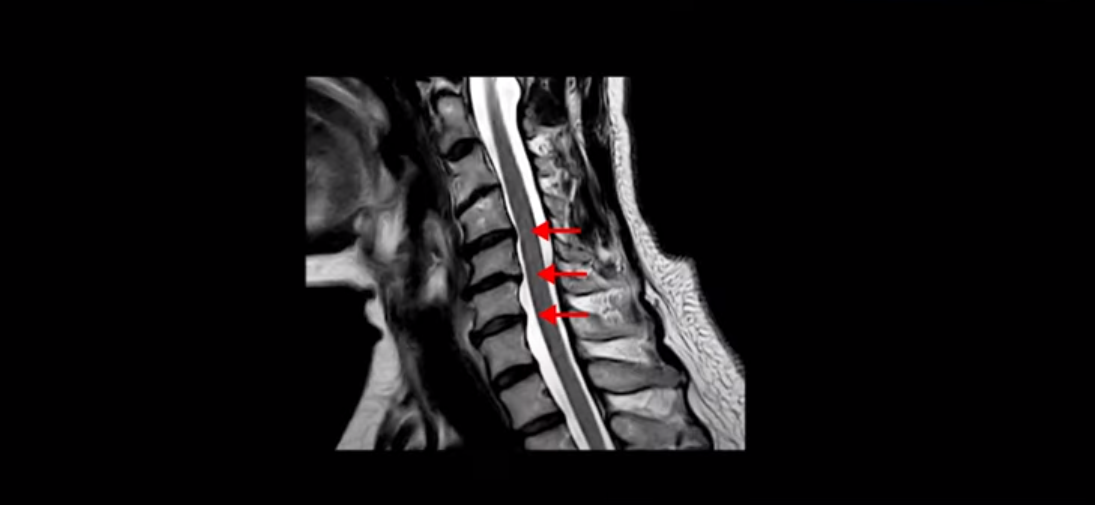

대학병원에 가서 MRI를 찍었는데 거기서도 디스크 증상이 있다고 했어요. 그리고 협착증 이런 게 있다고 했고 치료 방법 소개를 안 해주셨어요. 그냥 운동하라고만 얘기하시고 진통제 약만 주시고 그냥 내보냈어요. 어떻게 운동을 해야 될지도 모르겠고 운동하는 방법을 알려주는 데를 소개를 해주시든지 그냥 종이 보고 운동하라고 하시니까 내가 운동을 어떻게 해요. 혼자서 못하죠.

이 환자분 X-ray, MRI 보고 간단히 설명 드린 후 왜 목디스크 치료가 허리디스크에 비해 훨씬 더 쉬운지 자세히 설명 드리겠습니다.

MRI에서도 보시다시피 여러 마디에 퇴행성 디스크가 있습니다.

이런 걸 협착이라고 부르는 거죠. 이 분의 가장 불편한 증상은 20년간 아픈 만성적인 목통증과 어깨통증, 두통과 눈 통증인데 최근 들어 가증 불편한 증상은 목이 아예 돌아가지 않는 겁니다. 그래서 운전할 때도 사이드 미러를 보려면 몸을 돌리셨다고 하는데요. 주사 효과도 전혀 없고 대학병원에서도 디스크와 협착인데 그냥 약먹고 운동만 하라고 하면 이 환자는 어떻게 해야 할까요?

이 환자분도 아까 X-ray에서 보여드렸듯이 아주 심한 일자목, 거북목이 있고 그 결과로 목의 거의 모든 마디가 다 퇴행이 진행되어 있죠. 즉 거북목은 모든 목질환, 특히 목디스크, 목협착증의 어머니 질환이며 그래서 목디스크를 치료하기 위해서는 반드시 거북목 때문에 짧아지고 뭉치고 굳고 뒤틀린 목 주변 근육들을 잘 치료해줘야 합니다.